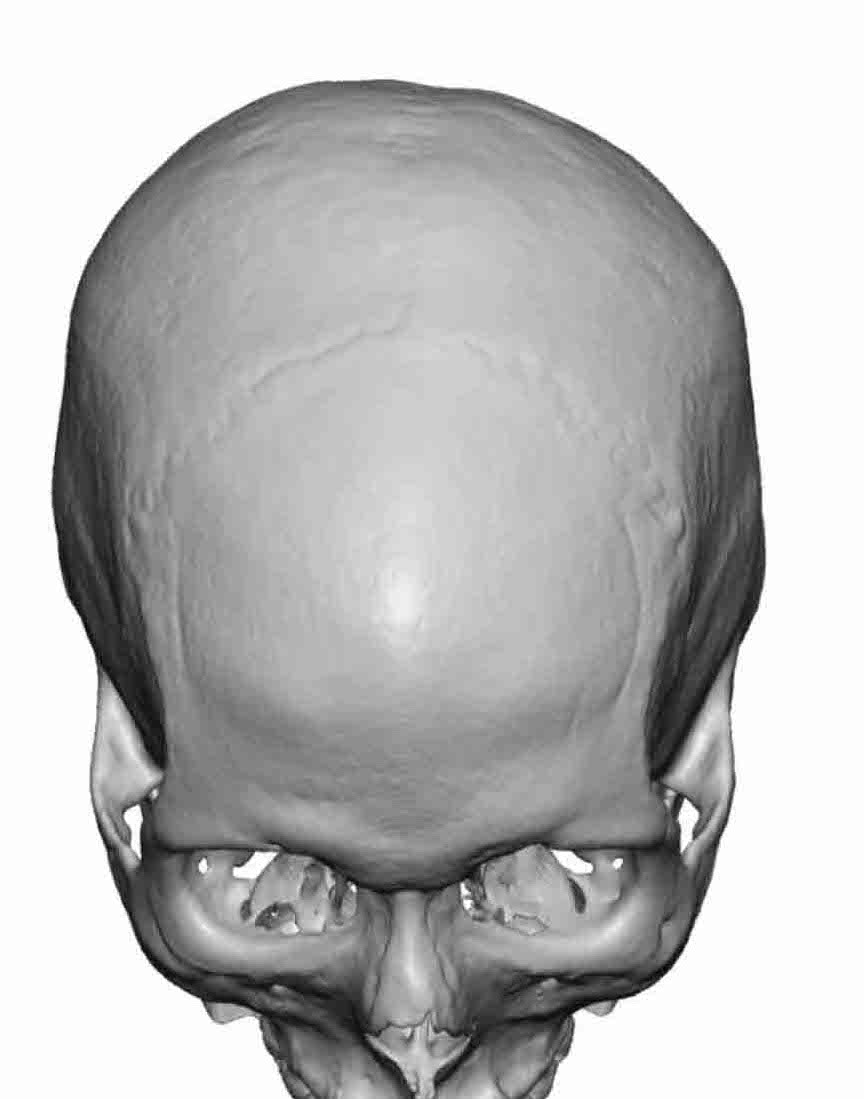

Patient 28

Desire for rounder shape to the top of the head from a congenital parasagittal deficiency skull shape.

Custom skull implant designed to fill in the parasagittal deficiencies.

Desire for rounder shape to the top of the head from a congenital parasagittal deficiency skull shape.

Custom skull implant designed to fill in the parasagittal deficiencies.